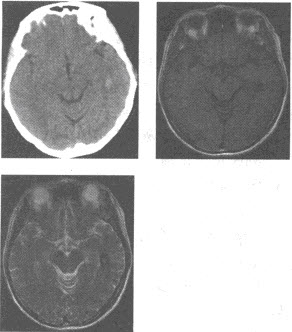

(单选题)该患者的CT所示,结合病史,该患者最可能的诊断是()

A:肺脓肿

B:肺癌

C:炎性假瘤

D:肺结核

E:转移瘤

F:大叶性肺炎

(单选题)本病最可能的病理类型为()

A:腺癌

B:小细胞癌

C:大细胞癌

D:鳞癌

E:鳞腺癌